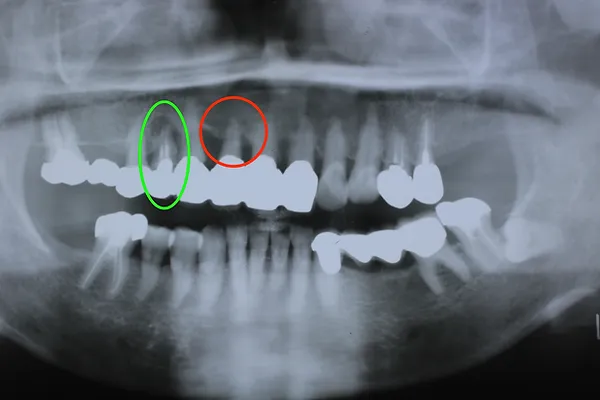

H31.2月には下の写真の青色に囲われた歯が根の先の病気でダメになり抜歯をすることになりましたが、歯の見えている部分はそのままで根だけを切って抜歯しました。そのため1本歯が少なくなり、9本で端から端まで繋がっています。

H31.2のレントゲン

下のレントゲン写真はR3.12月に撮影した写真ですが、赤丸の歯槽膿漏の歯は1枚目のH22.5月の頃からほとんど変化しておらず、13年経っても大丈夫です。全部の歯が繋がっていて、1本1本の歯の動きがないため、長く維持できています。

R3.12のレントゲン